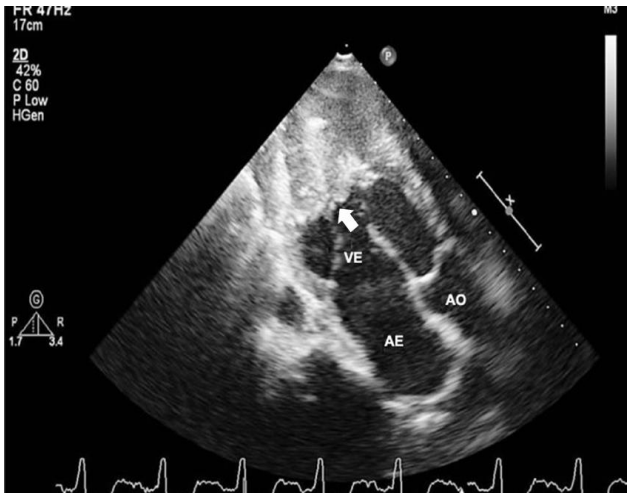

Analise a imagem a seguir.

(VE: ventrículo esquerdo; AE: átrio esquerdo; AO: aorta)

Entre as possíveis etiologias de miocardiopatias restritivas apresentadas a seguir, a mais associada ao padrão de obliteração apical fibrótica e/ou trombótica de um ou ambos os ventrículos, conforme visualizado no ecocardiograma acima(seta), é a